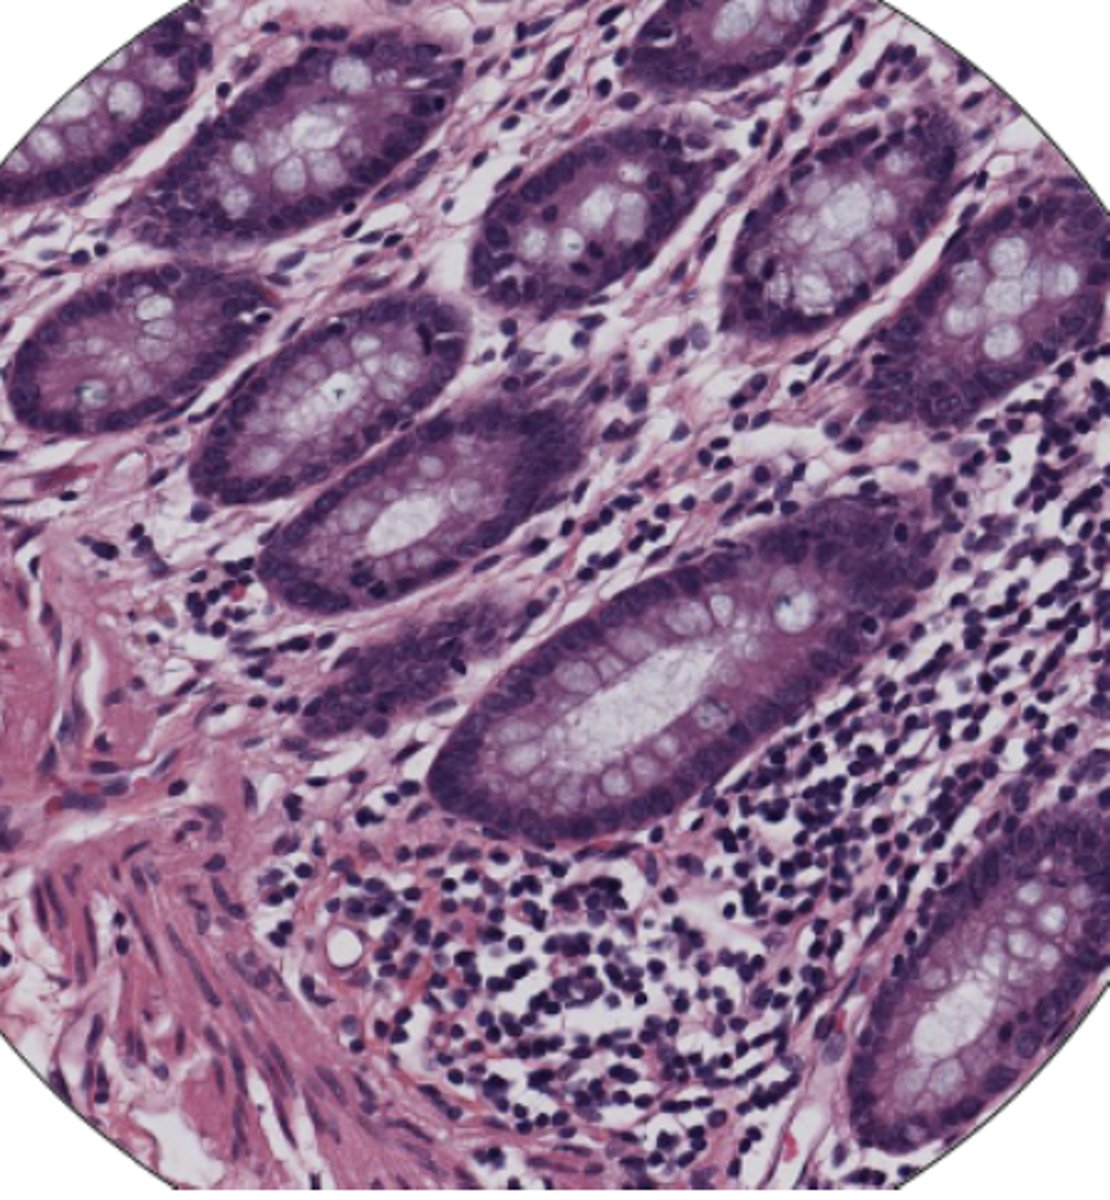

LI mucosa layer (100)

LI mucosa layer (400)